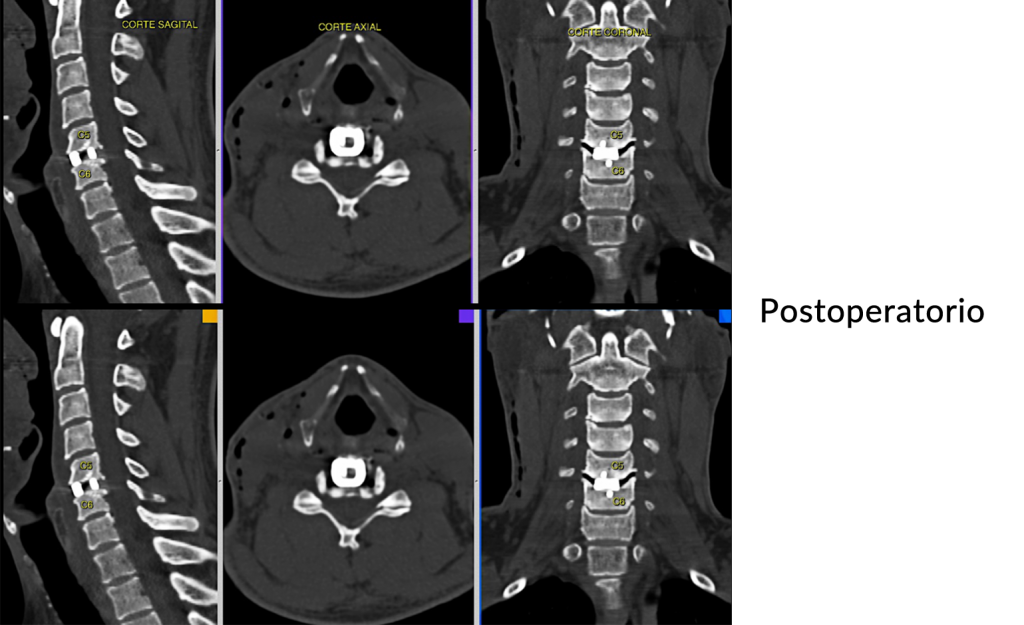

Hernia de

disco cervical